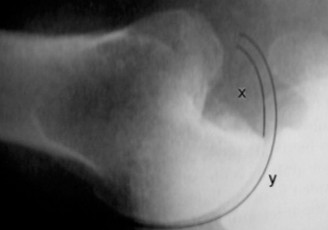

Rotator cuff tears are a common reason for shoulder pain and a common reason to obtain shoulder imaging. As a result, numerous different imaging modalities exist offering different pros and cons. Plain films are still the initial imaging modality of choice. These are most useful in ruling out other possible diagnosis but can help with the diagnosis of a rotator cuff tear as well. Changes to the tendon itself

may appear as calcific tendinosis, which would most commonly be seen at the bone–tendon interface. A decrease in the acromiohumeral distance (less than 2 mm) may also be indicative of a cuff tear. In late cases of rotator cuff tears, superior subluxation of the humerus may be evident. Certain variations in acromial anatomy, including spurs or a hook-shaped (type 3) acromions, may be associated with rotator cuff tears as well. With progression of rotator cuff tears, degenerative changes including spurs, cysts, and sclerosis may be evident at the greater tuberosity. In late, massive tears one may see degenerative changes consistent with rotator cuff arthropathy.